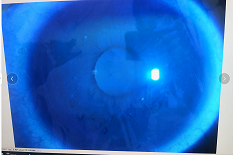

圓錐角膜要做那種治療比較好

【文章導(dǎo)讀】圓錐角膜的治療應(yīng)該依據(jù)角膜發(fā)展的時(shí)期選擇。目前圓錐角膜按照臨床癥狀大致可以分為四個(gè)時(shí)期,分別為潛伏期、初發(fā)期、完成期和瘢痕期,各個(gè)時(shí)期的主要癥狀表現(xiàn)如下: 潛伏期:

圓錐角膜的治療應(yīng)該依據(jù)角膜發(fā)展的時(shí)期選擇。目前圓錐角膜按照臨床癥狀大致可以分為四個(gè)時(shí)期,分別為潛伏期、初發(fā)期、完成期和瘢痕期,各個(gè)時(shí)期的主要癥狀表現(xiàn)如下:

完成期:發(fā)展迅速,角膜明顯前突,視力銳減。

瘢痕期:角膜急性角膜水腫、混濁,消退后基質(zhì)層殘留瘢痕。

圓錐角膜的形成機(jī)制就是膠原變薄,變?nèi)?。圓錐角膜患者的角膜膠原變薄了以后,彈性增加,正常的眼壓會(huì)使角膜向前膨隆。